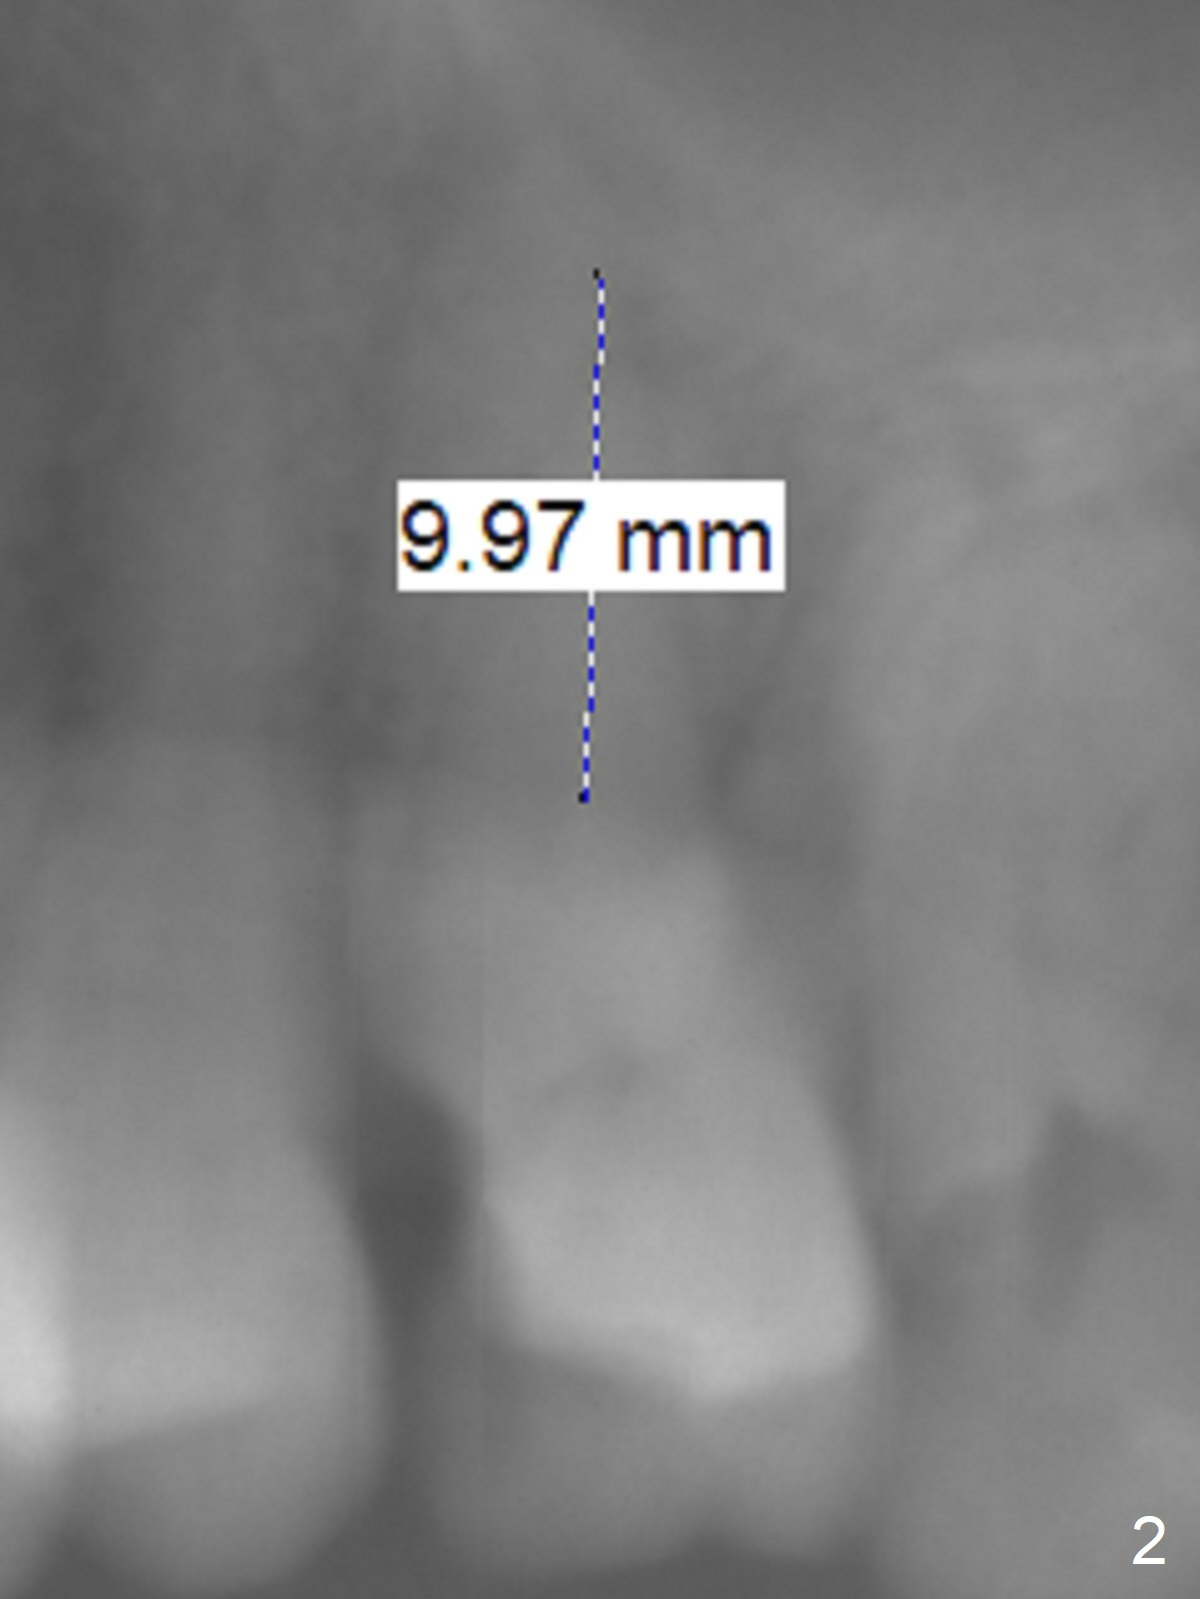

Osteotomy 1-2 mm from Sinus Floor

A 65-year-old woman cracks the tooth #14 prior to #4 implant (Fig.1). The height of the septum is ~ 10 mm; initial osteotomy depth will be 8.5 mm; 1-2 mm from the sinus floor. While increasing the drill size, check whether there is perforation on the side of the osteotomy apically. Since the patient is small, start low dose of X-ray.